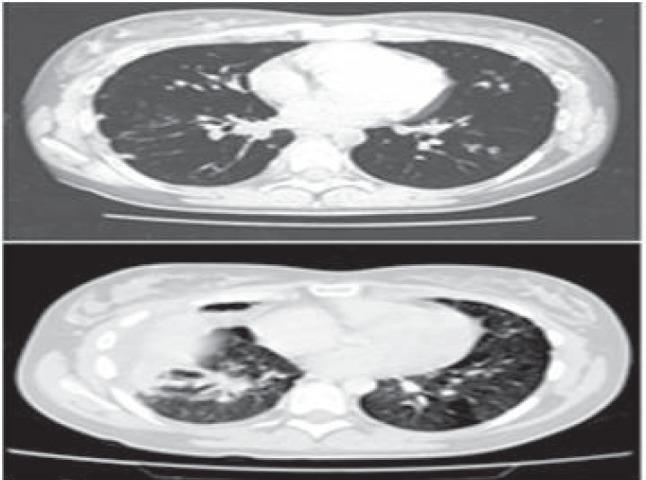

In this report we describe a case of pulmonary epithelioid hemangioendothelioma (PEH) in a young woman. The neoplasm manifested with dry cough, chest pain, finger clubbing, and multiple bilateral pulmonary nodules on chest x-ray and computed tomographic (CT) scan. She underwent thoracoscopy, and the histological features of the lung biopsies were initially interpreted as consistent with a not-well-defined interstitial lung disease. Our patient was clinically and radiologically stable over a period of four years, after which the disease progressed to involve not only the lung but also mediastinal lymph nodes, liver and bone. Fiberoptic bronchoscopy showed subtotal occlusion of the right middle and lower lobe bronchi. The histologic examination of bronchial biopsies revealed a poorly differentiated neoplasm immunohistochemically positive for vimentin and vascular markers CD31, CD34 and Factor VIII. A diagnosis of malignant hemangioendothelioma was made. Positron emission tomography (PET) is more sensitive than CT scan and bone scintigraphy in detecting PEH metastases. Furthermore, 18-fluorodeoxyglucose (FDG) uptake seems to be related to the grade of malignancy of PEH lesions. Therefore, we suggest that FDG-PET should be included in the staging system and follow-up of PEH.

在本报告中,我们描述了一名年轻女性患肺上皮样血管内皮瘤(PEH)的病例。该肿瘤表现为干咳、胸痛、杵状指,胸部X线和计算机断层扫描(CT)显示双侧肺部有多个结节。她接受了胸腔镜检查,肺活检的组织学特征最初被解释为与一种界限不清的间质性肺病相符。我们的患者在四年时间里临床和放射学表现稳定,此后病情进展,不仅累及肺部,还累及纵隔淋巴结、肝脏和骨骼。纤维支气管镜检查显示右中叶和下叶支气管部分阻塞。支气管活检的组织学检查显示为低分化肿瘤,免疫组化显示波形蛋白及血管标志物CD31、CD34和因子VIII呈阳性。诊断为恶性血管内皮瘤。正电子发射断层扫描(PET)在检测PEH转移方面比CT扫描和骨闪烁显像更敏感。此外,18-氟脱氧葡萄糖(FDG)摄取似乎与PEH病变的恶性程度有关。因此,我们建议FDG-PET应纳入PEH的分期系统和随访中。